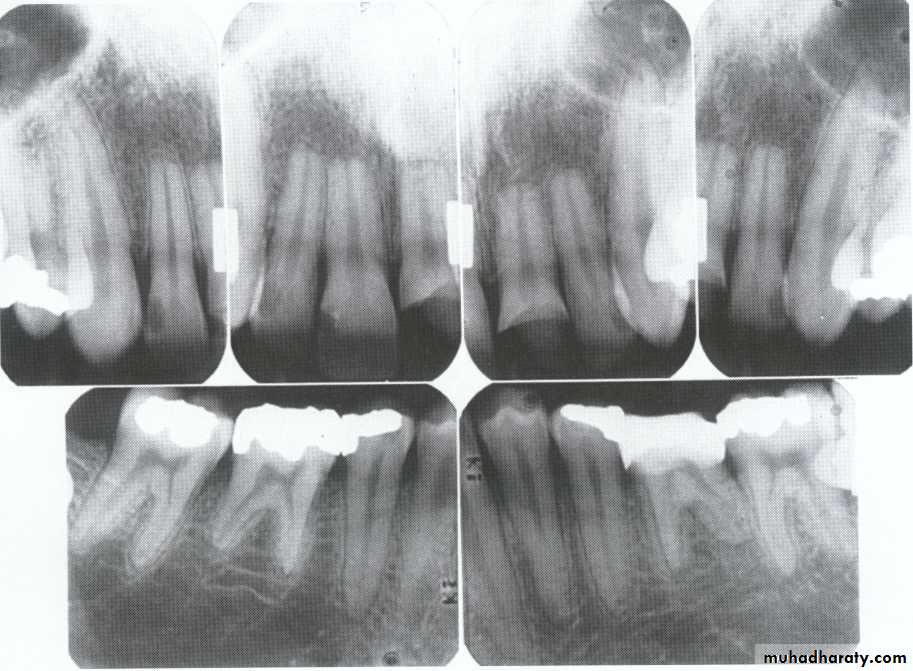

Radiographically:

Deciduous teeth:

roots are extremely short

pulps almost completely obliterated

Permanent teeth:

abnormally large pulp chambers in coronal portion of tooth.

Type II (Coronal Type)

Dentin dysplasia, type II. panoramic &periapical films of the same case show obliteration of the pulp chamber, reduction in the caliber of root canals, and pulp stones obscuring the flame-shaped pulp chambers.

Periapical inflammatory lesions are associated with some of the mandibular anterior teeth.